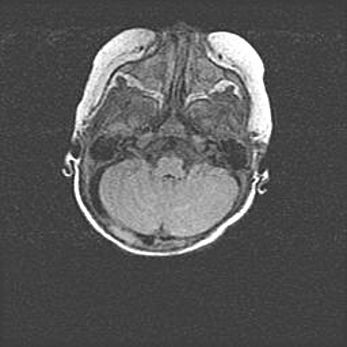

Подострая гематома правой гемисферы мозжечка.

Наружная гидроцефалия.

Возраст: 15 дней

Вес: 3100 г

Пол: женский

Окружность головы: 37 см

Срок гестации: 35-36 недель

При открытой наружной форме гидроцефалии у новорожденных расширяются и переполняются субарахноидные пространства.

Кровоизлияния в мозжечок имеют две клинико-анатомические формы: полушарные гематомы и кровоизлияния в червь.

К появлению этой патологии может привести: повреждения головного мозга, возникающие в результате асфиксии и гипоксии плода при беременности, или травмы во время родов. Редко гематома мозжечка может быть результатом первичной коагулопатии и сосудистой мальформации, диссеминированном внутрисосудистом свертывании, изоиммунной тромбоцитопении.